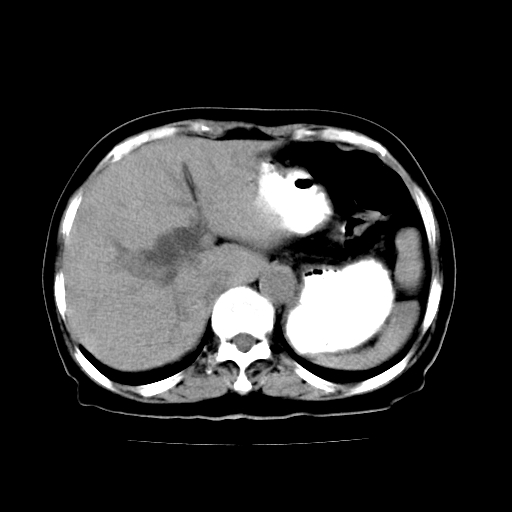

女,74岁,上腹部不适、腹胀两月余,黄染四天。请大家看看肿块周围血管情况。

肝内外胆管 胆囊及胆总管明显扩张,胆总管末端逐渐变细,并见不规则软组织肿块,明显强化.考虑:胆总管末端占位_首先考虑胆总管癌.

肝内外胆管及胆囊扩张,胰管扩张,但“双管征”不明显,胆总管下段内见软组织有强化影,肠系膜上静脉推移不是很明显,考虑胆总管下段癌可能大。

胆囊胆总管扩张,胰头与十二指肠间似有一软组织密度灶,胰头增强不均,1壶腹癌,2胰头癌